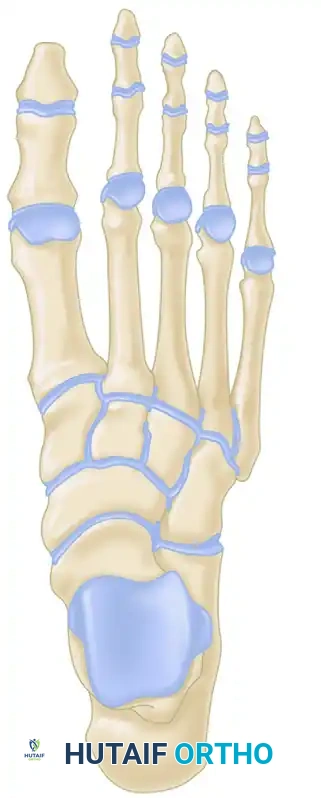

The fundamental goal of the Cotton osteotomy is to restore the tripod effect of the foot—specifically, the weight-bearing distribution between the calcaneal tuberosity, the fifth metatarsal head, and the first metatarsal head.

By plantarflexing the medial column through the medial cuneiform, the surgeon effectively re-establishes the medial pillar of this triangle, ensuring a plantigrade foot following hindfoot correction.